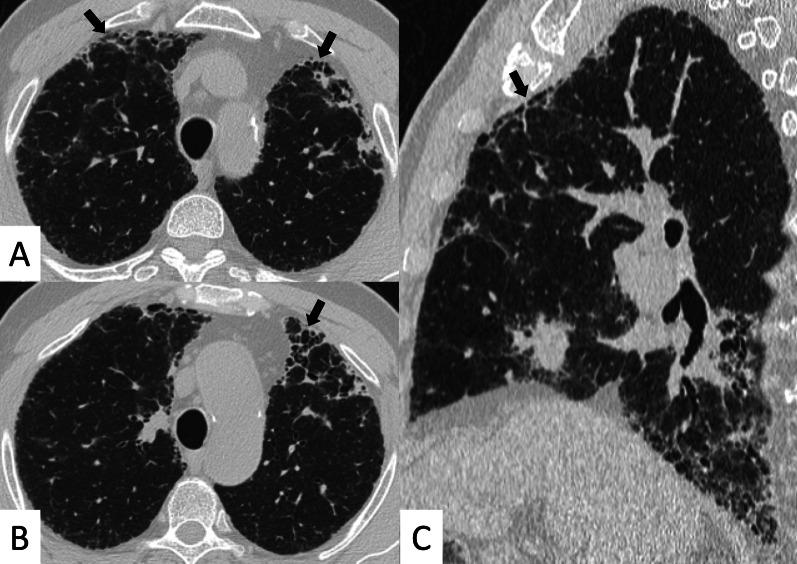

Connective tissue diseases (CTDs) include a spectrum of disorders that affect the connective tissue of the human body; they include autoimmune disorders characterized by immune-mediated chronic inflammation and the development of fibrosis. Lung involvement can be misdiagnosed, since pulmonary alterations preceded osteo-articular manifestations only in 20% of cases and they have no clear clinical findings in the early phases. All pulmonary structures may be interested: pulmonary interstitium, airways, pleura and respiratory muscles. Among these autoimmune disorders, rheumatoid arthritis (RA) is characterized by usual interstitial pneumonia (UIP), pulmonary nodules and airway disease with air-trapping, whereas non-specific interstitial pneumonia (NSIP), pulmonary hypertension and esophageal dilatation are frequently revealed in systemic sclerosis (SSc). NSIP and organizing pneumonia (OP) may be found in patients having polymyositis (PM) and dermatomyositis (DM); in some cases, perilobular consolidations and reverse halo-sign areas may be observed. Systemic lupus erythematosus (SLE) is characterized by serositis, acute lupus pneumonitis and alveolar hemorrhage. In the Sjögren syndrome (SS), the most frequent pattern encountered on HRCT images is represented by NSIP; UIP and lymphocytic interstitial pneumonia (LIP) are reported with a lower frequency. Finally, fibrotic NSIP may be the interstitial disease observed in patients having mixed connective tissue diseases (MCTD). This pictorial review therefore aims to provide clinical features and imaging findings associated with autoimmune CTDs, in order to help radiologists, pneumologists and rheumatologists in their diagnoses and management.

结缔组织病(CTDs)包括一系列影响人体结缔组织的疾病;它们包括以免疫介导的慢性炎症和纤维化发展为特征的自身免疫性疾病。肺部受累可能会被误诊,因为肺部改变仅在20%的病例中先于骨关节炎表现出现,且在早期阶段没有明确的临床发现。所有肺部结构都可能受累:肺间质、气道、胸膜和呼吸肌。在这些自身免疫性疾病中,类风湿关节炎(RA)的特征是普通型间质性肺炎(UIP)、肺结节和伴有空气潴留的气道疾病,而系统性硬化症(SSc)常表现为非特异性间质性肺炎(NSIP)、肺动脉高压和食管扩张。NSIP和机化性肺炎(OP)可见于多发性肌炎(PM)和皮肌炎(DM)患者;在某些情况下,可观察到小叶周围实变和反晕征区域。系统性红斑狼疮(SLE)的特征是浆膜炎、急性狼疮性肺炎和肺泡出血。在干燥综合征(SS)中,HRCT图像上最常见的表现是NSIP;UIP和淋巴细胞间质性肺炎(LIP)的报道频率较低。最后,纤维化NSIP可能是混合性结缔组织病(MCTD)患者中观察到的间质性疾病。因此,本图像综述旨在提供与自身免疫性CTDs相关的临床特征和影像学表现,以帮助放射科医生、呼吸科医生和风湿病科医生进行诊断和管理。